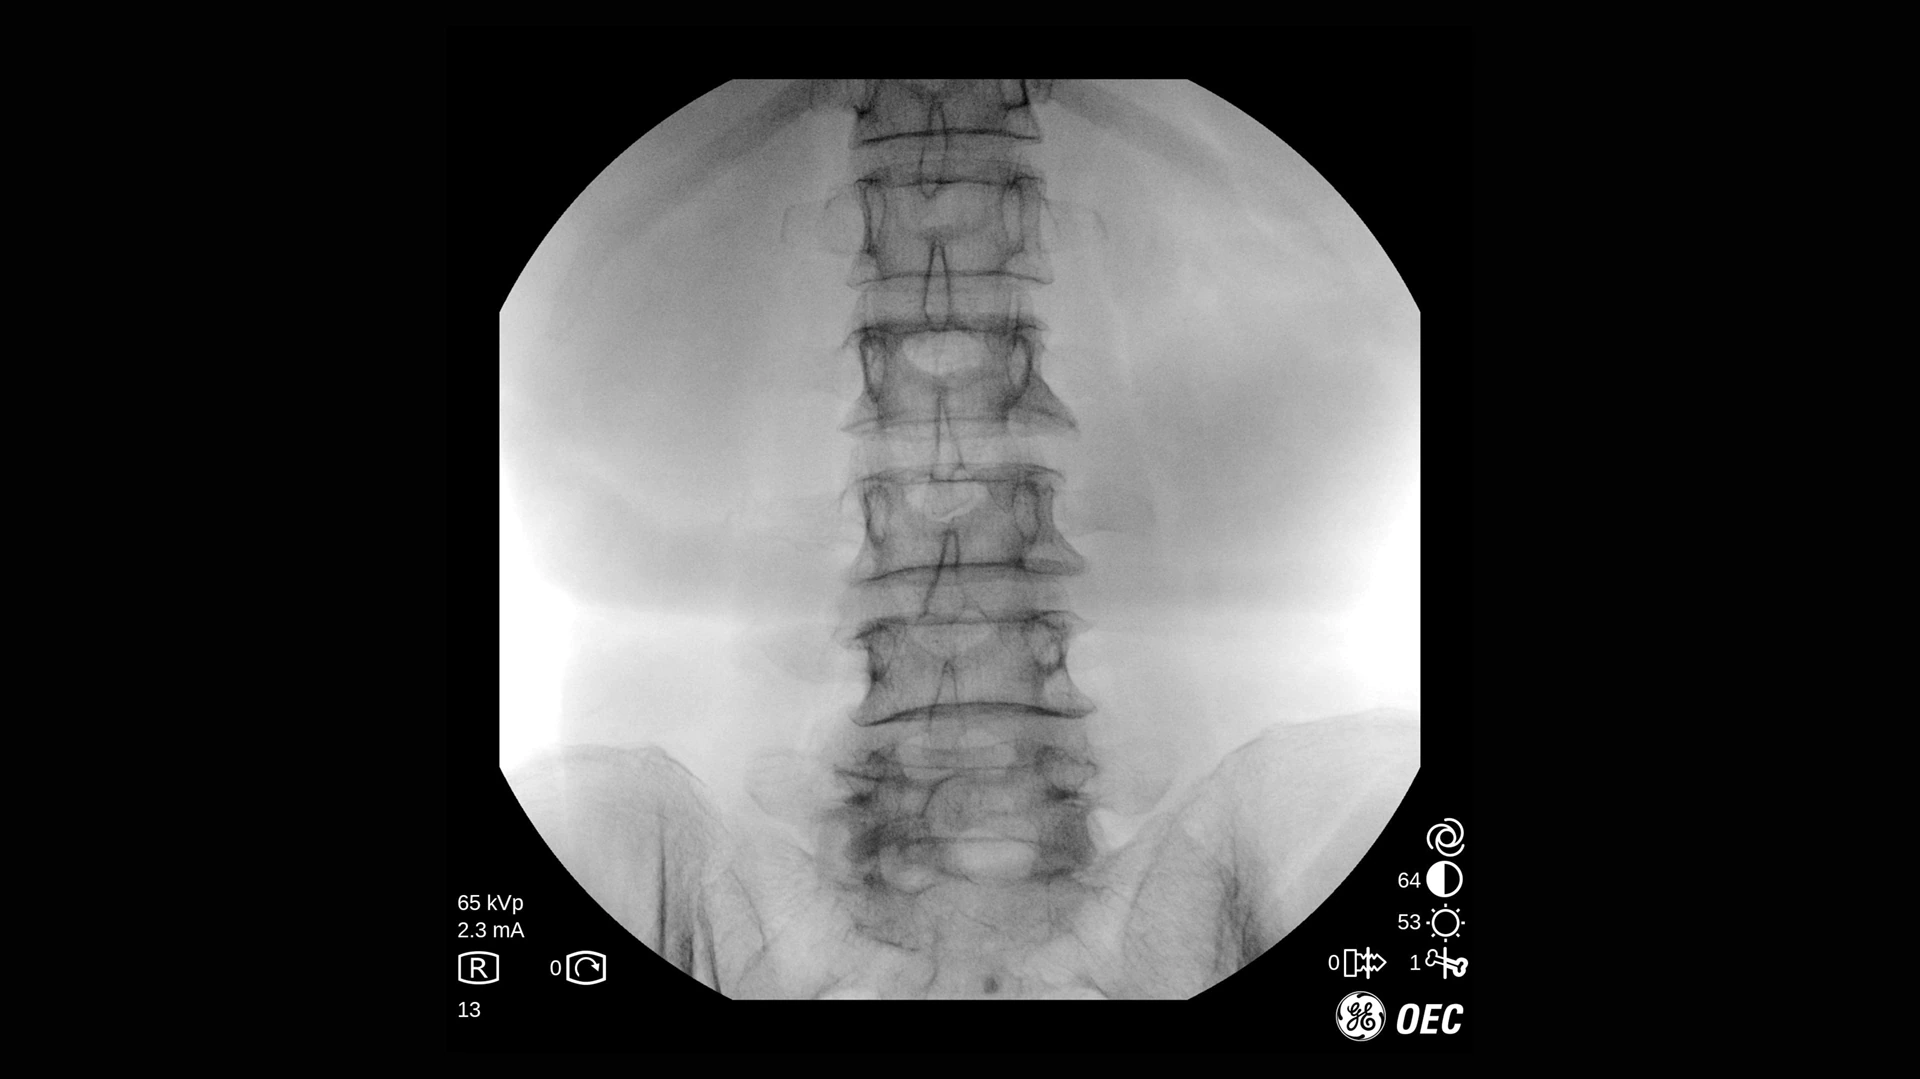

GE Healthcare OEC One CFD относится к классу мобильных рентгеновских аппаратов с С-образной дугой, в которых все ключевые узлы — излучатель, детектор, монитор и панель управления — объединены в единую компактную конструкцию. КМОП-плоскопанельный детектор и фирменная цепочка обработки Clear View обеспечивают высокую детализацию изображения в широком спектре клинических задач: от рутинных травматолого-ортопедических вмешательств до эндоваскулярных процедур и сложной спинальной хирургии. Интеллектуальные алгоритмы подавления помех от металлоконструкций, автоматической оптимизации окна и уровня, а также режимы увеличения позволяют уверенно визуализировать мелкие структуры, проводники и импланты без существенного роста дозовой нагрузки.

- Режимы рентгеноскопии, цифрового снимка и субтракционной ангиографии для интраоперационного контроля хода вмешательств.

- Специализированные клинические профили для ортопедии, спинальной хирургии, общей хирургии, урологии, сосудистых и болевых процедур.